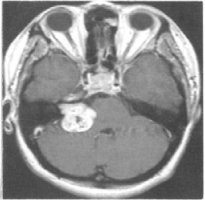

73 47 歲女性,主訴近五個月來,右側耳鳴、聽力減退, 根據所附 MRI 圖(T1WI with Gd-DTPA),則其診斷 是: (A) CP angle tentorial meningioma (B) CP angle aneurysm (C) Acoustic neurinoma (D) Pontine glioma